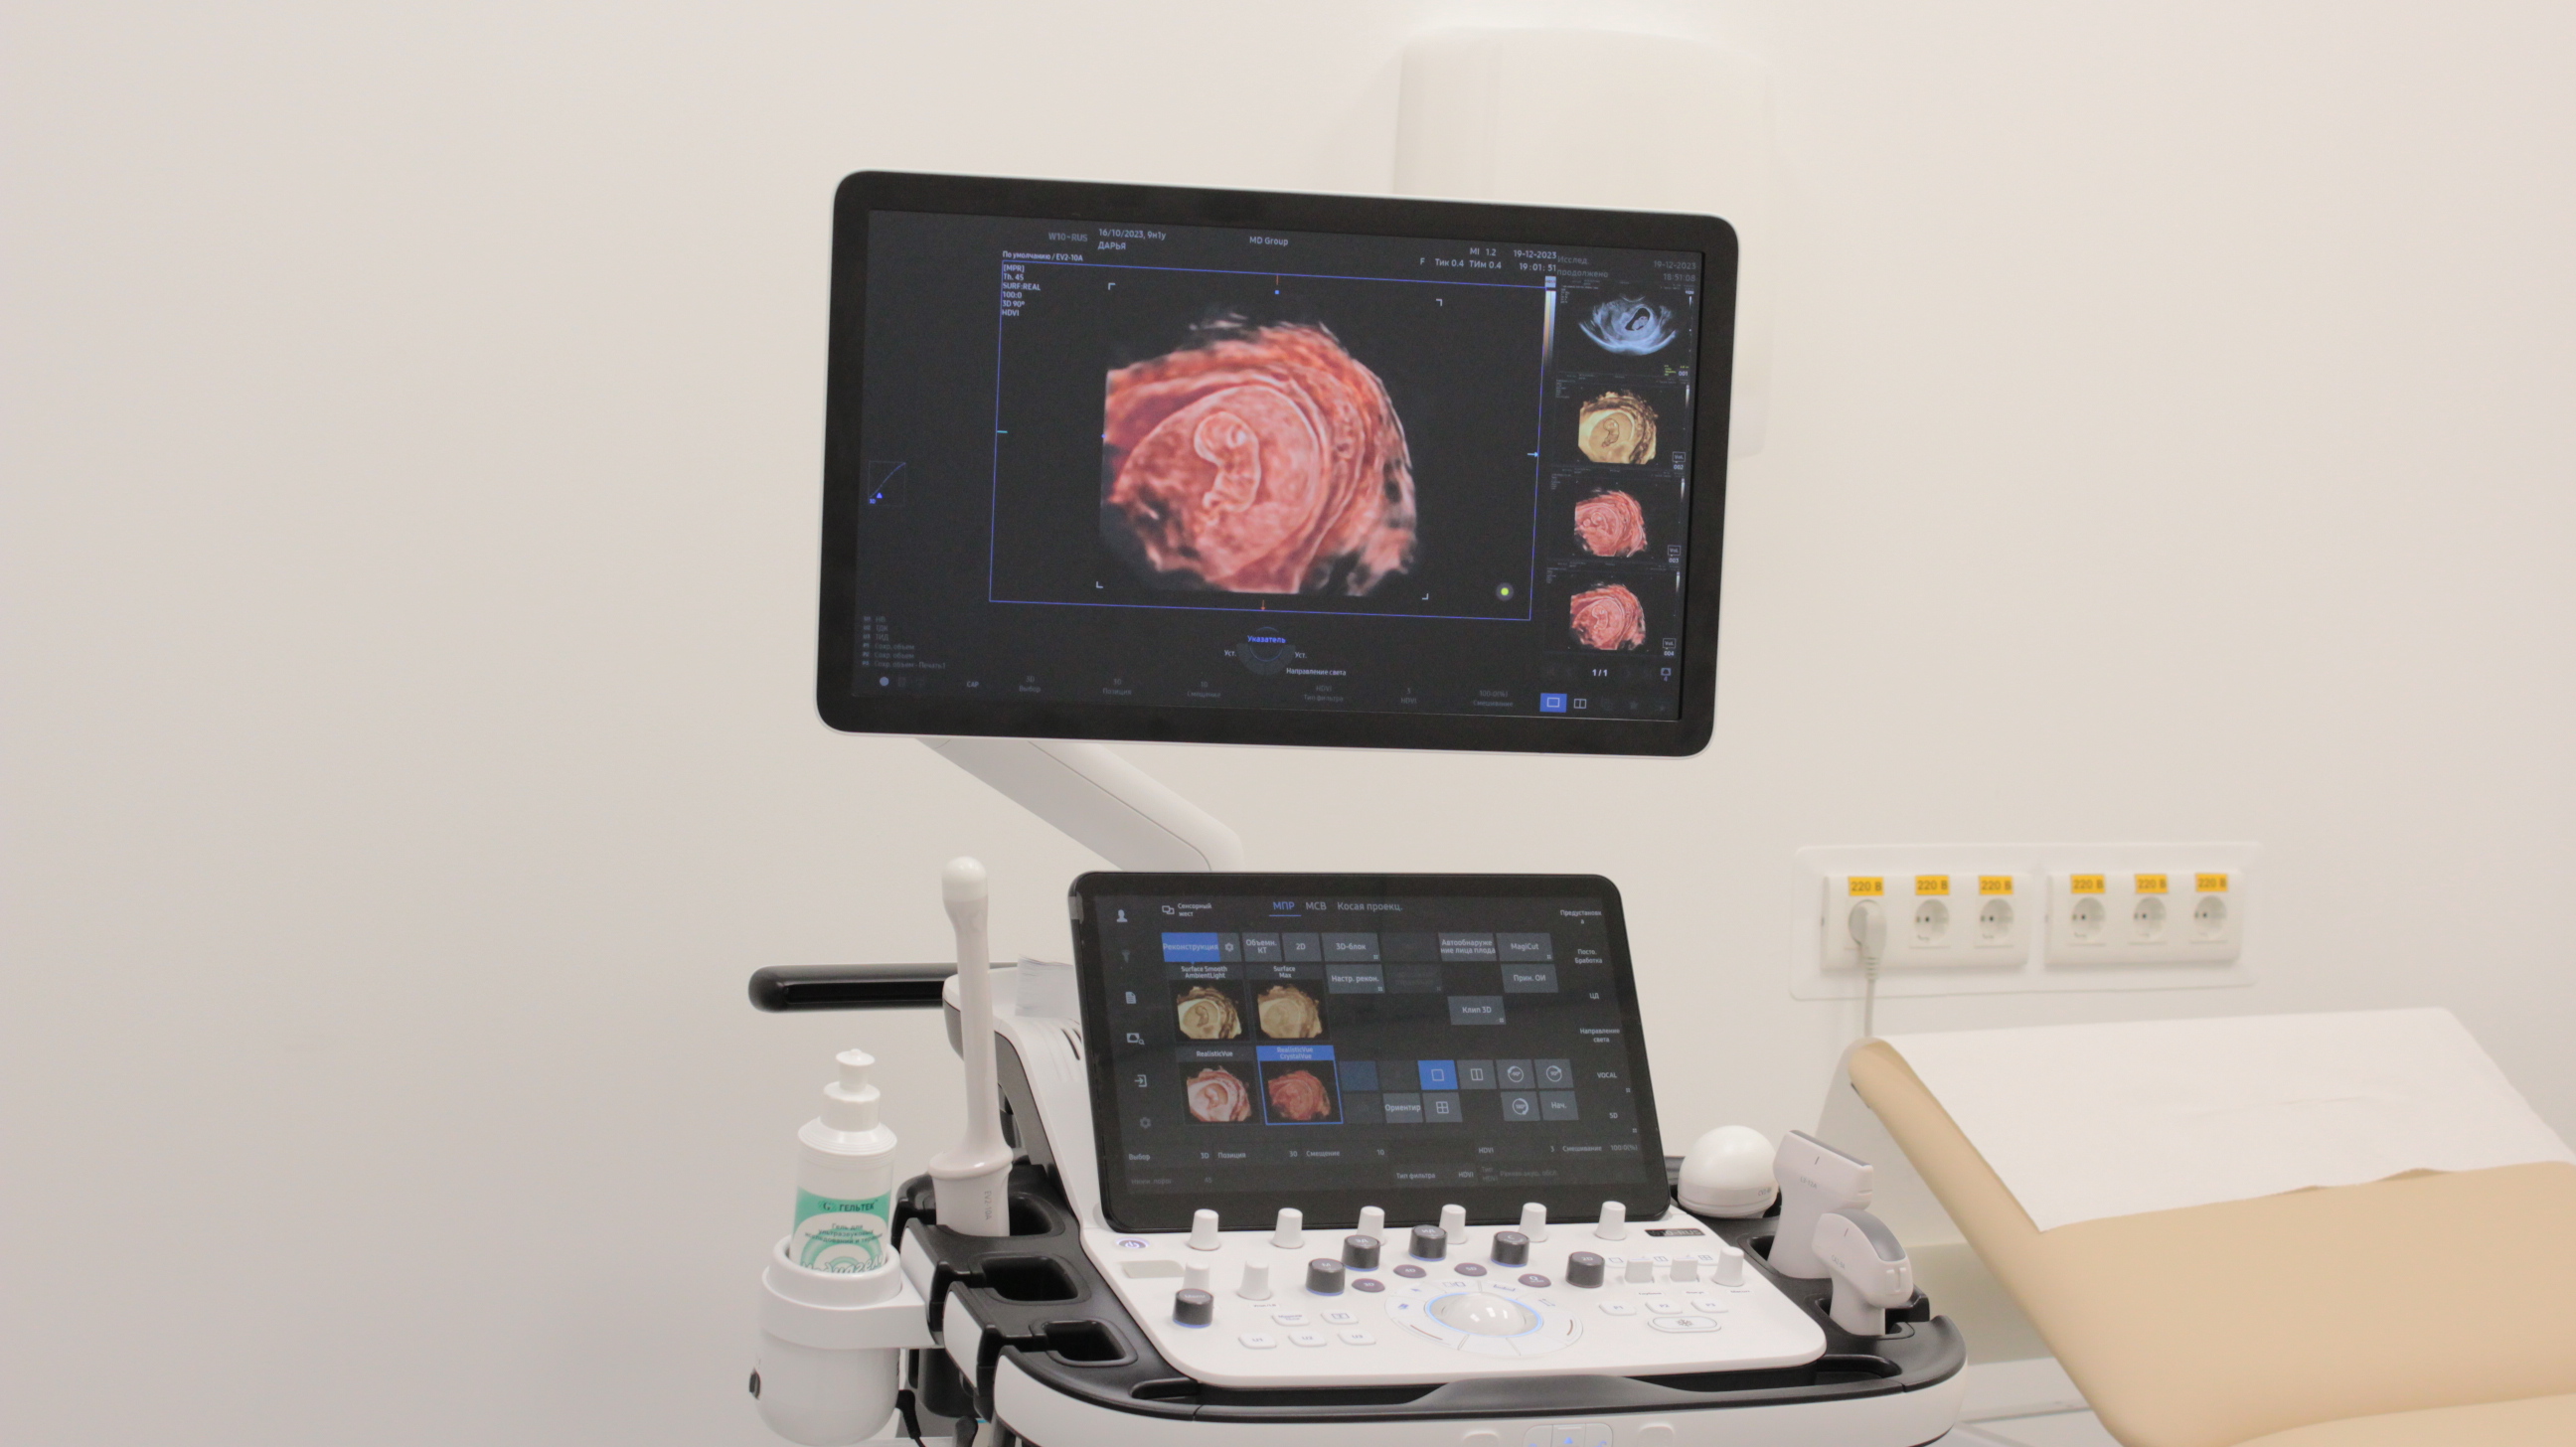

Ультразвуковое исследование – это наиболее информативный метод диагностики состояния плода и беременной женщины. В «Мать и дитя» оно проводится с помощью современного ультразвукового оборудования, которое формирует максимально детализированное изображение. УЗИ дает возможность обнаружить особенности развития малыша на самой ранней стадии. Метод абсолютно безопасен и может выполняться любое количество раз.